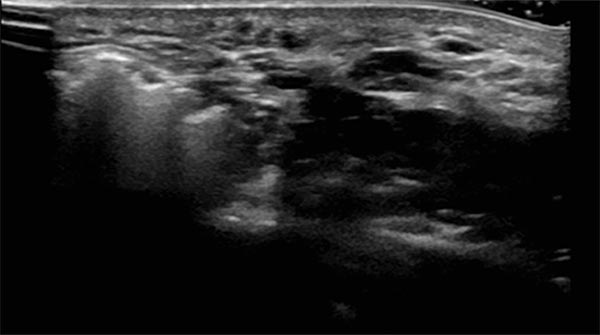

Sonography during sclerotherapy treatment. At the right side of the picture the still unfilled parts of the venous malformation, shown black as nearly echo-free vascular channels. On the left side lesion already filled by the sclerosing foam, echogenic with dorsal acoustic shadowing.

Sonography during sclerotherapy treatment. Now further filling of the venous malformation by the sclerosing foam. When the entire malformation is filled with the foam, the injection can be terminated.